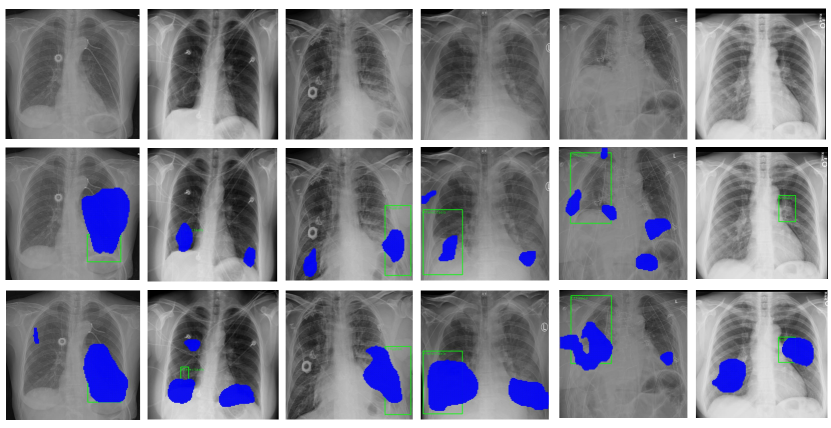

In this task, we adopt images with only image-level labels for training, and images with both bounding box and class annotations for testing. We compare our method against various existing methods proposed in [1, 4, 30, 3, 5, 29]. As shown in Table 4, our method achieves the best performance in overall. Compared to the baseline model [5], our method achieves consistently higher accuracy under all IoU thresholds. For example, in case of using 0.3 as IoU threshold, it produces results with accuracy of 0.48, surpassing [5] by 0.02. When threshold of IoU is set as 0.5 and 0.7, our approach achieves accuracy of 0.36 and 0.21, with a lead of 0.01 and 0.02 over [5], respectively. In Fig. 8, we illustrate disease detection results of several cases under the condition of the weak supervision. From top to down are original images, results of [5], and results produced by our method. The green boxes stand for ground-truths and blue regions indicate predictions inferred by disease localization models. The results verify the effectiveness of our method in weakly supervised disease detection. Following [38], we generate a critical difference diagram for comparing our method against other weakly supervised methods, based on the Wilcoxon-Holm method 222https://github.com/hfawaz/cd-diagram/. The mean accuracies under different IoUs are used as the input. As shown in Fig. 6, our proposed method achieves the best rank.